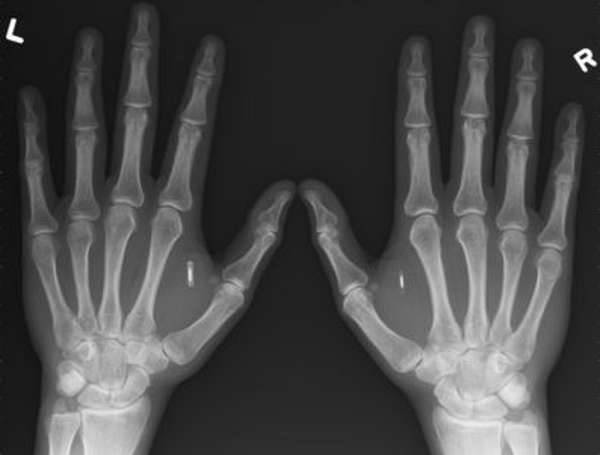

«Это средство лечит суставы даже в самых безнадежных случаях при переломах, вывиха и растяжениях»Читать далее…, Переломы руки могут быть как открытыми, так и закрытыми. При закрытом переломе организм без проблем для самого больного начинает срастание. Неправильное срастание в большинстве случаев происходит из-за неправильного лечения. При открытых переломах пациент может столкнуться с другими трудностями, например инфекции или развитие остеомиелита.

Перелом руки может срастись неправильно по следующим причинам:

- лечение производилось неверно,

- смещение произошло в повязке,

- травматолог не установил петли, которые вправляют кость,

- при оперативном лечении фиксаторы были установлены не по морфологии.

Как видно, причиной неправильного срастания может служить только ошибка в самом лечении

Если сделать рентгеновский снимок через три недели, то на нем можно будет увидеть костную мозоль в месте срастания. То, что перелом срастается неправильно, можно обнаружить с помощью рентгена именно на этом этапе. Что делать с неправильно сросшимся переломом, решается в каждом индивидуальном случае по разному.